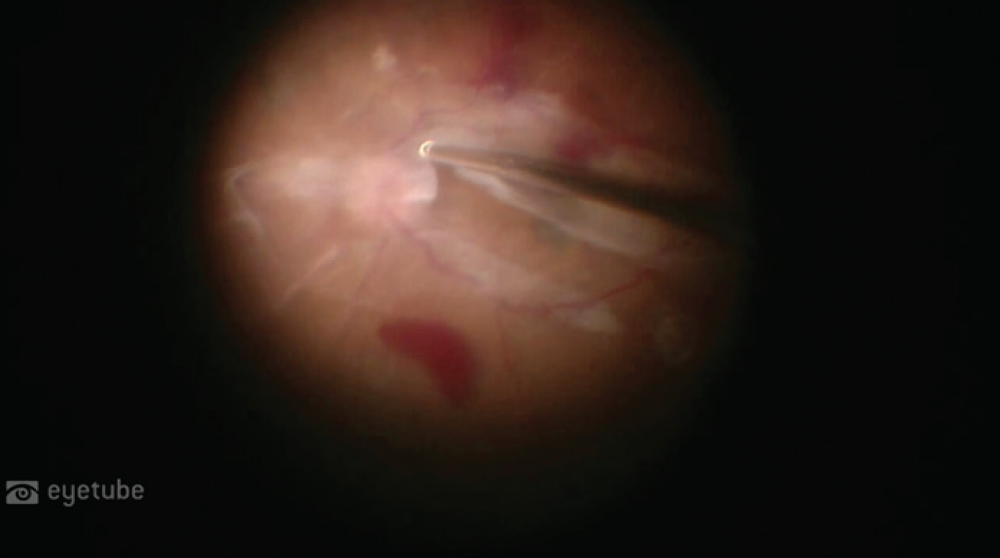

Case No. 5: Repair of a Chronic Macular Hole

From Diana V. Do, MD; and Peter H. Tang, MD, PhD: We present a case of a 62-year-old pseudophakic woman with counting fingers vision and stable diabetic retinopathy who presented for treatment of a large, persistent macular hole in her right eye. There had been three attempts at repair prior to her presentation. Autologous serum and amniotic membranes were used to close the macular hole.

Commentary from Dr. Klufas: Should we try to close holes with retinal grafts? With autologous serum and amniotic membrane? If so, is one preferred over the other? Some argue that retinal grafting is more effective. Others note that application of autologous serum and amniotic membrane is easier to perform.